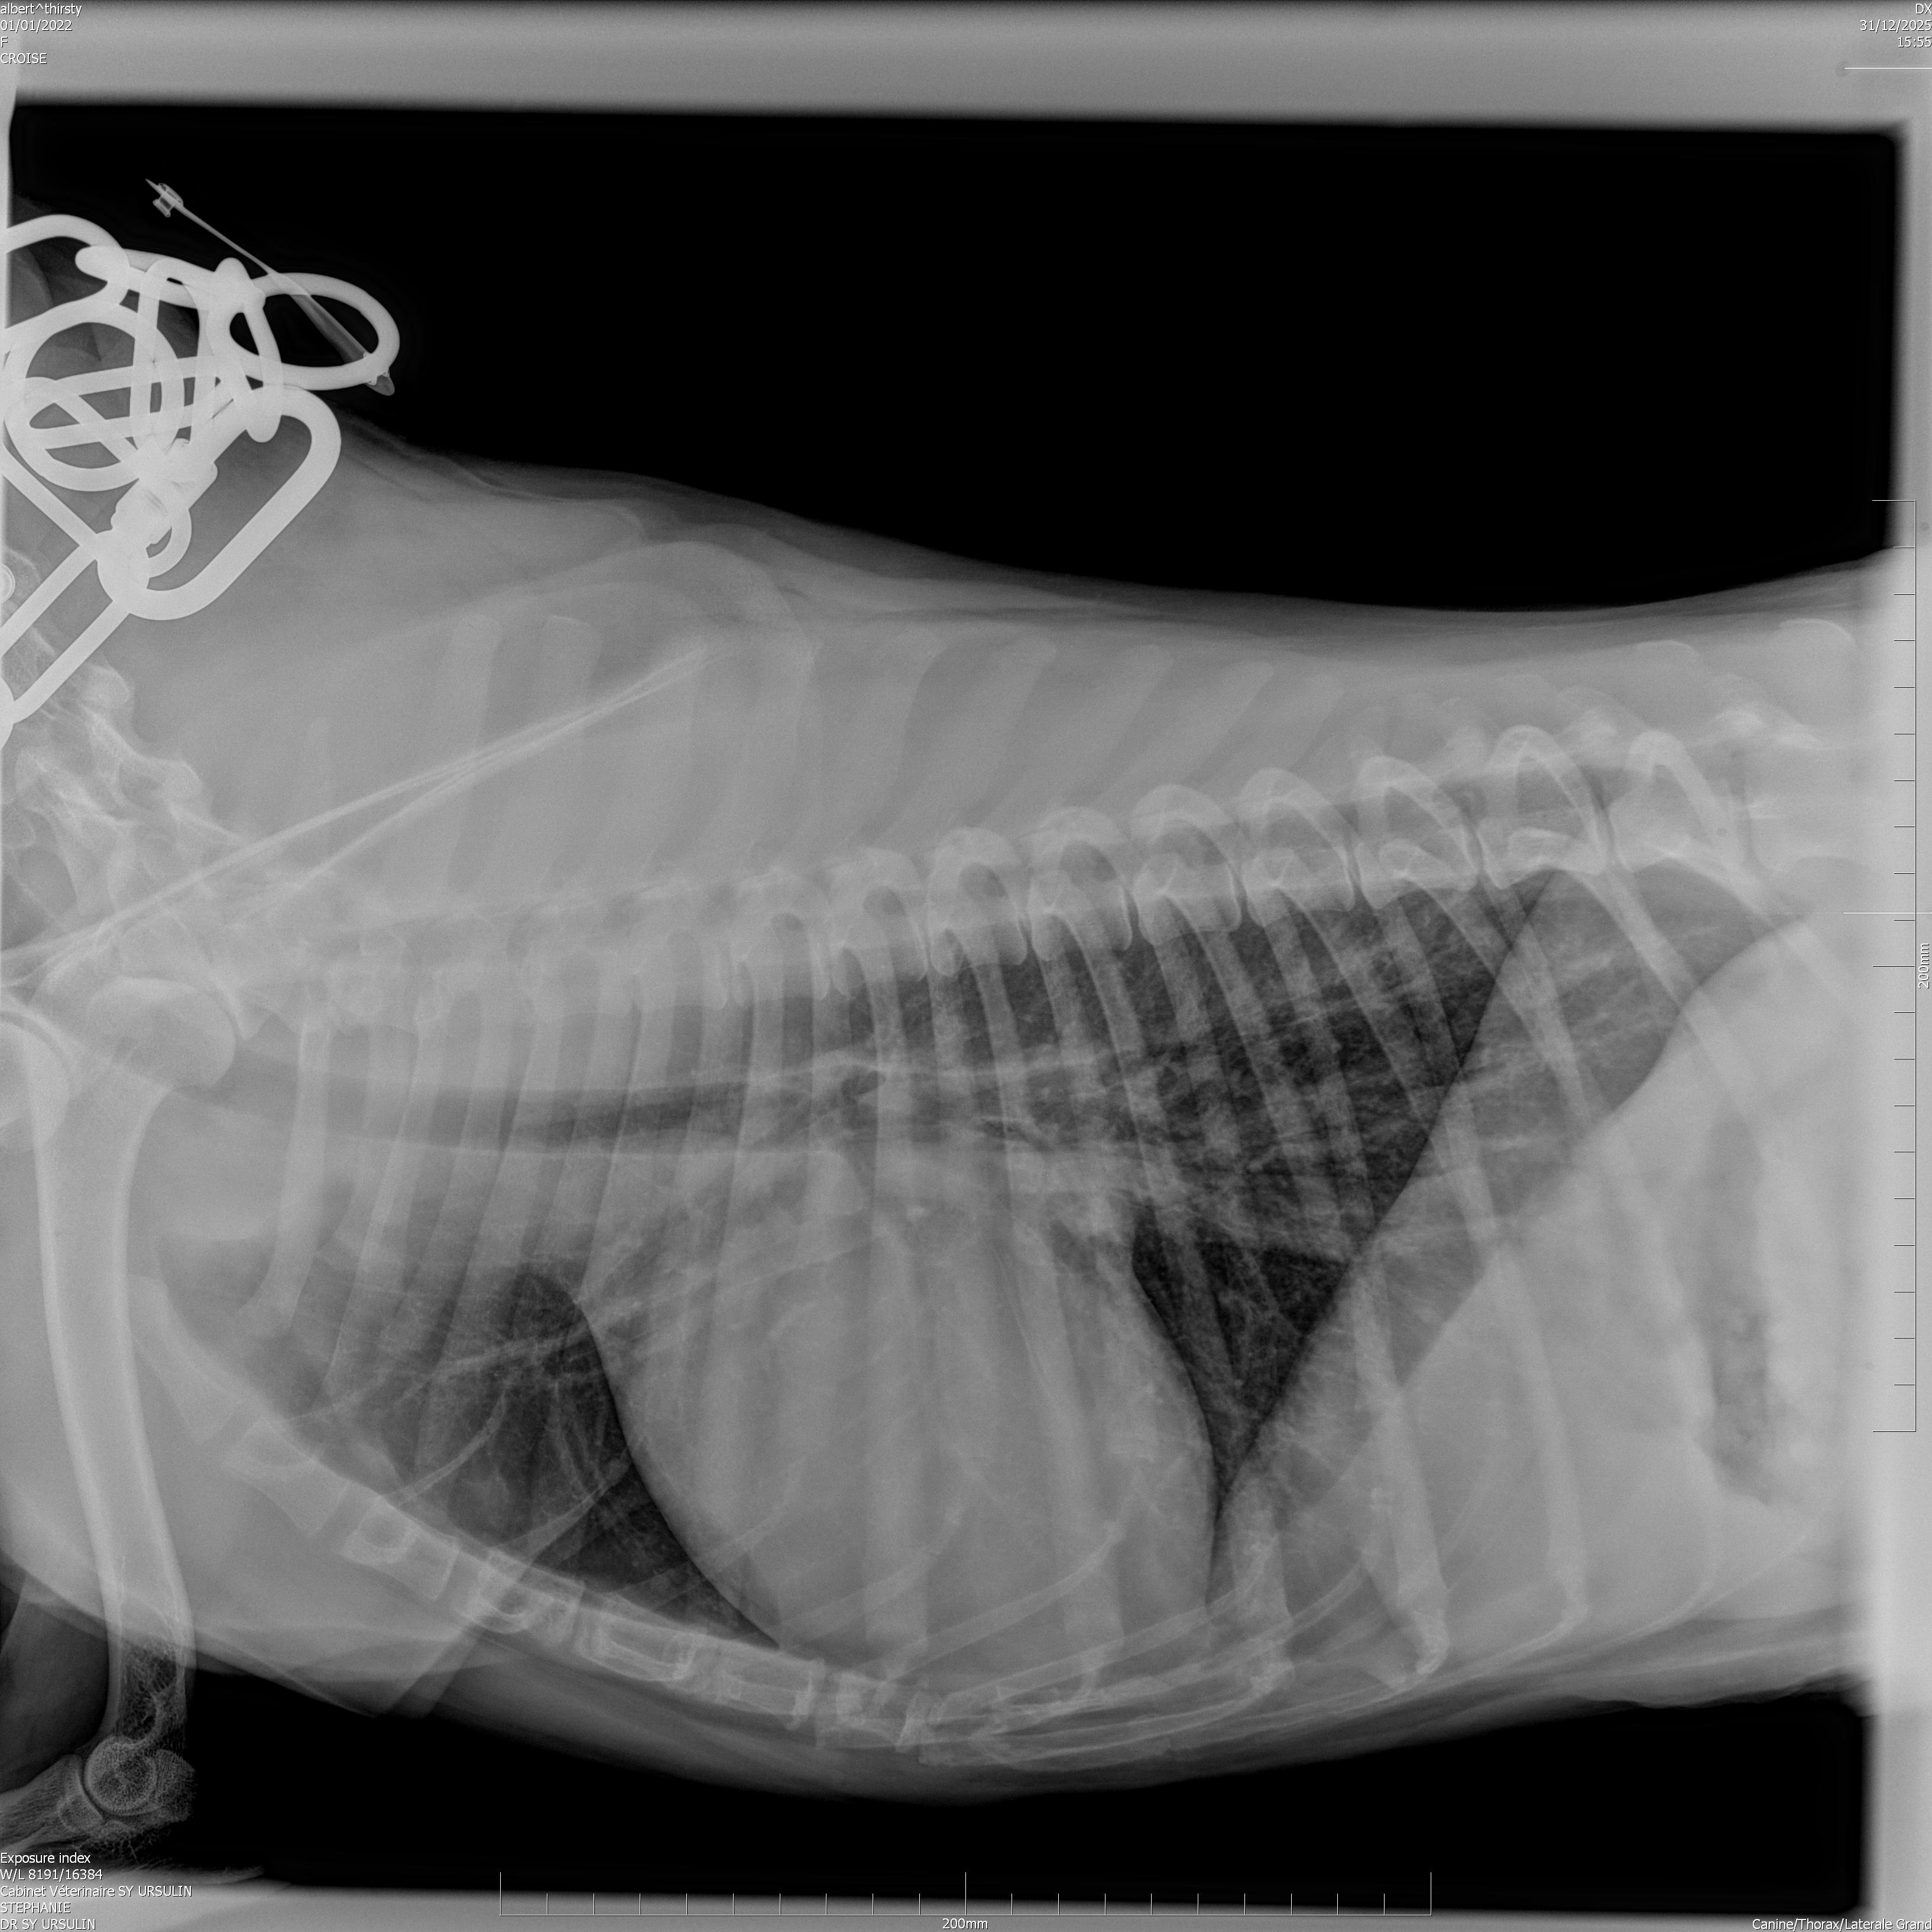

Geste technique : Mesure échographique du LA/Ao (rapport oreillette gauche/aorte)

Echographie

Cardiologie